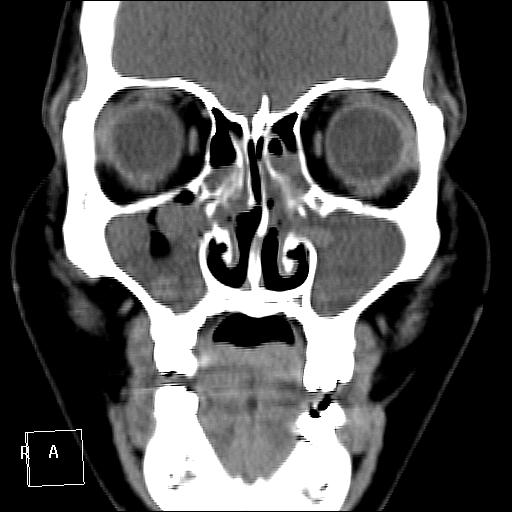

КТ ППН и носоглотки. Девушка 21 года. Полипозный риносинусит.

Госпитализирована для оперативного лечения. Удалены полипы носа. Вторым этапом планируется гайморотомия. Во время операции - подозрение на образование носоглотки. Сохраняется затруднение носового дыхания. Направлена на КТ. Категорически отказалась от контрастировния (лекарственная полиаллергия, боится).

Полип в носоглотке справа. Нарушена пневматизация придаточных пазух носа кроме левой решётчатой. В левой гайморовой на дне неясно что…

На дне гайморовой - полип, в носоглотке немаленький хоанальный полип. Там всё в полипах, а они и фиброзные бывают, и ангиофибромы, и ангиоаденомы... Вот и плотность разная.

Ну, как-то все в одну кучу - и полипы, и ангиофибромы. При ангиофиброме, например, околоносовые пазухи свободны. А гиперденсность более характерна для грибкового поражения (аспергилеза), в том числе и "севшим" на пломбировочный материал.

На операции визуально полипы аденоматозного типа. Какие будут гистологически после гайморотомии - сейчас трудно сказать. Если б гиперденсность была только по нижней стенке верхнечелюстной пазухи, тогда вариант с аспергиллезом на пломбировочном материале, на мой взгляд, был бы более вероятен. У девушки участки гиперденсности по всем стенкам верхнечелюстных пазух, в основной пазухе, совсем чуть - в решетчатом лабиринте слева, без костной деструкции. Без посева и гистологии - только гадать)). В носовой полости признаков грибкового поражения ЛОРы не отмечают. Но Вы правы, может иметь место изолированное поражение синусов.